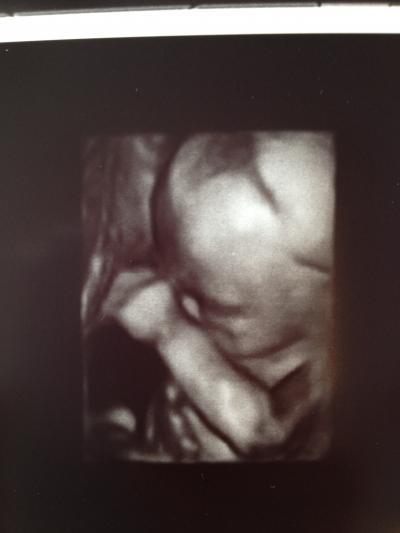

Morgen Bin wieder zurück vom Termin und noch immer ganz verliebt Der Kleine war wohl erst am schlafen und wurde dann vom Arzt "wachgerüttelt", hat sich prompt gedreht und angefangen zu zappeln und am Daumen zu lutschen. Voll süß Letztlich lag er gut und der Arzt konnte sich alles in Ruhe anschauen und vermessen. Herz, Lunge, Nieren, Plazenta, Blutfluss, Nabelschnur, Fruchtwasser, Gehirn usw. ist alles so wie es sein sollte und es gab keine Auffälligkeiten. Männe war auch dabei und ganz glücklich. Jetzt bin ich echt erleichtert und hoffe, dass die SS weiterhin so unbeschwert bleibt :-) Hab leider nur vergessen nach der Gesamtgröße zu fragen und muss mir das noch aus allen vermessenen Einzelgrößen zusammenrechnen... Hänge mal noch ein paar Bildchen ran. Leider hatte er auf den 3D-Bildern immer den Arm vorm Gesicht. Aber ich bekomm ja bei meiner Ärztin auch nochmal die Chance auf tolle 3D-Bilder. Ist mal wieder richtig lang geworden Liebe Grüße von der glücklichen Tina

Toll, das Alles gut ist mit dem Kleinen ! Freut mich sehr für Dich! Wundervolle Bildchen hast Du da von Deinem Prinzen ... Auf dem 2. sieht er aus, als würde er lachen, echt sweet ! LG Mone